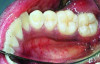

The MGJ was delineated by the visual method and the roll method following clinical examination in dental chairs appropriately equipped. Visual assessment relies on identifying the color difference between the gingiva and alveolar mucosa. The mucosa beyond the MGJ typically appears darker red compared to the AG, helping to demarcate the MGJ. The rolling probe method entails pushing the neighboring alveolar mucosa coronally with the blunt end of a probe. It is a functional assessment method that aids in determining the boundary between gingiva and movable mucosa.10 The probing sulcus depth was subtracted from the measured KG width at the mid-lingual aspect of each tooth to determine the width of AG, and all fractional measurements were rounded off to the nearest whole number of millimeters (Figure 1 through Figure 3).

Fig 2 = sulcus depth measurement.

Figure 2

Fig 4 through Fig 6. Lingual attached gingiva in a male subject: Fig 4 = left side.

Figure 4

Fig 5 = middle.

Figure 5

Fig 6 = right side.

Figure 6